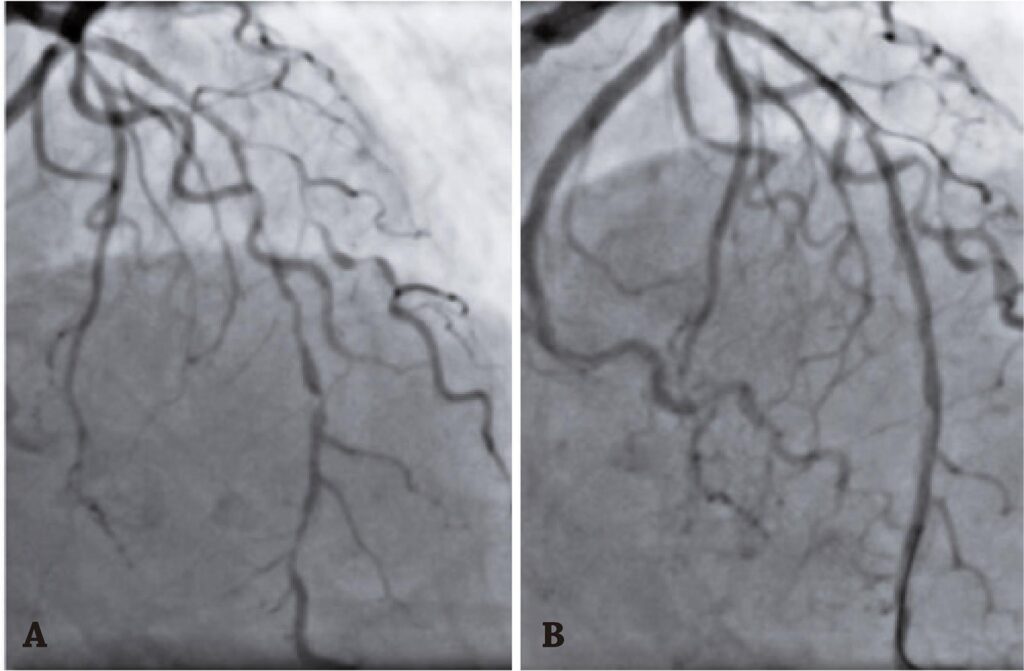

Figura 1

(A) Lesão aterosclerótica difusa em artéria descendente anterior. (B) Pré-dilatação de artéria descendente anterior.